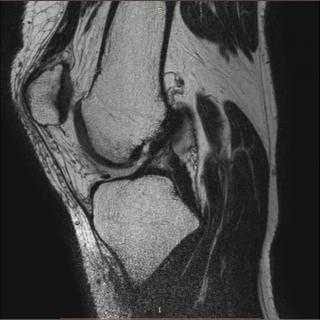

Расшифровка

На серии МР-томограмм визуализированы структуры левого голеностопного сустава. Соотношения в голеностопном, подтаранном суставах не нарушены, патологического выпота в полости голеностопного сустава не выявлено. Синовиальная оболочка не дифференцируется. Хрящевое покрытие голеностопного, подтаранного и таранно-ладьевидного суставов неравномерно истончено. Суставные полости голеностопного, подтаранного и таранно-ладьевидного суставов слева умеренно неравномерно сужены.

Медиальные отделы: патологических сигналов от медиальной лодыжки не выявлено. В краевых медиальных отделах блока таранной кости субхондрально отмечается локальный участок эрозирования размером ~ 2-3мм, без патологических изменений в смежных трабекулярных отделах. Дельтовидная связка определяется на всем протяжении, сигнал от связки неоднородный, общее натяжение связки сохранено. Сухожилия длинного сгибателя большого пальца, длинного сгибателей пальцев, задней большеберцовой мышцы однородной структуры.

Латеральные отделы: патологических сигналов от латеральной лодыжки не выявлено. Передняя и задняя нижние межберцовые связки сохранены, межберцовый синдесмоз равномерный на всем протяжении. Передняя таранно-малоберцовая связка определяется на всем протяжении, истончена, отмечается слабоинтенсивное повышение сигнала от связки, общая целостность сохранена. Задняя таранно-малоберцовая связка не изменена. Пяточно-малоберцовая связка прослеживается на всем протяжении, типичной структуры. Структура сухожилий малоберцовых мышц однородная, определяется скопление жидкости перитендинозно сухожилиям короткой и длинной малоберцовой мышц.

Задние отделы: определяется удлинение латерального бугорка заднего отростка таранной кости, без патологических изменений сигнала от прилежащих отделов жировой клетчатки, отмечается локальное скопление однородной жидкости в данной зоне. В задних отделах пяточной кости, в области пяточного бугра, субкортикально отмечается локальный участок эрозирования размером ~ 3-4мм, без патологических изменений в смежных трабекулярных отделах. Определяется шиповидное костное разрастание в задненижних отделах пяточной кости, на уровне прикрепления подошвенной фасции и короткого сгибателя пальцев, без патологических изменений сигнала от данной фасции. Пяточное сухожилие однородной структуры. Клетчатка Кагера без особенностей. Тарзальный канал не изменен.

Передние отделы: сухожилия передней большеберцовой мышцы, разгибателей пальцев стопы и большого пальца равномерны по толщине и интенсивности сигнала. Плюсневая пазуха без особенностей.

Заключение: МР-картина частичного повреждения дельтовидной и передней таранно-малоберцовой связок. МР-признаки деформирующего артроза голеностопного, подтаранного и таранно-ладьевидного суставов 1-2ст. Теносиновит сухожилий малоберцовых мышц.